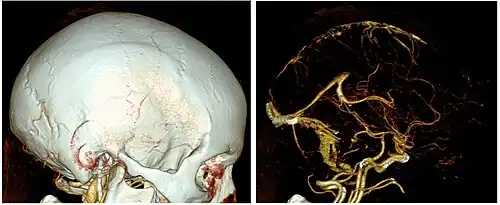

In scientific visualization and computer graphics, volume rendering is a set of techniques used to display a 2D projection of a 3D discretely sampled data set, typically a 3D scalar field.

A typical 3D data set is a group of 2D slice images acquired by a CT, MRI, or MicroCT scanner. Usually these are acquired in a regular pattern (e.g., one slice for each millimeter of depth) and usually have a regular number of image pixels in a regular pattern. This is an example of a regular volumetric grid, with each volume element, or voxel represented by a single value that is obtained by sampling the immediate area surrounding the voxel.

To render a 2D projection of the 3D data set, one first needs to define a camera in space relative to the volume. Also, one needs to define the opacity and color of every voxel. This is usually defined using an RGBA (for red, green, blue, alpha) transfer function that defines the RGBA value for every possible voxel value.

For example, a volume may be viewed by extracting isosurfaces (surfaces of equal values) from the volume and rendering them as polygonal meshes or by rendering the volume directly as a block of data. The marching cubes algorithm is a common technique for extracting an isosurface from volume data. Direct volume rendering is a computationally intensive task that may be performed in several ways.

Volume rendering is distinguished from thin slice tomography presentations, and is also generally distinguished from projections of 3D models, including maximum intensity projection.[1] Still, technically, all volume renderings become projections when viewed on a 2-dimensional display, making the distinction between projections and volume renderings a bit vague. Nevertheless, the epitomes of volume rendering models feature a mix of for example coloring[2] and shading[3] in order to create realistic and/or observable representations.

A direct volume renderer[4][5] requires every sample value to be mapped to opacity and a color. This is done with a "transfer function" which can be a simple ramp, a piecewise linear function or an arbitrary table. Once converted to an RGBA color model (for red, green, blue, alpha) value, the composed RGBA result is projected on the corresponding pixel of the frame buffer. The way this is done depends on the rendering technique.